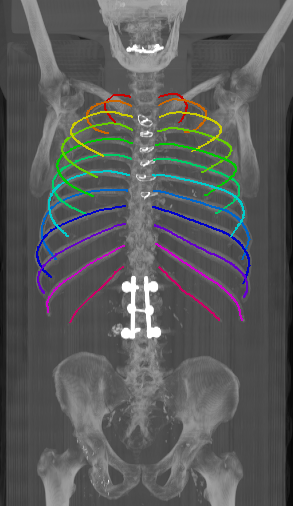

As can be seen from Table 2, we obtain overall good performance for the overall rib detection captured for example with an mean Dice of 0.84. Let us remark that for thin objects, such as the dilated rib centerlines, the Dice score constitutes a rather sensitive measure. The results indicate that detecting the first and twelfth rib pairs is more difficult for our network. While extraction of the first rib is more challenging due to, e.g., higher noise in the upper thorax or other bony structures in close vicinity (clavicle, shoulder blades, vertebrae), the twelfth rib can be extremely short and is easily confused by the neighboring ribs. For further illustration, Figure 4 shows the results on selected representative cases. Generally, the ribs are well detected without major false responses in other structures - despite all the different challenges present in the data. The color coding highlighting of the multi-label detection reveals that first and twelfth are mostly correctly detected. In few cases the network wrongly generated strong responses of the classes first rib or last rib for voxels belonging to the second or eleventh rib pair.

Refer to caption

Figure 4: Maximum intensity projections (MIP) of selected CT volumes overlaid with the multi-label output of the neural network (green: first rib; red: intermediate rib; blue: twelfth rib). The selected case above display common difficulties which are inherent in the data set, such as pads (a) or cables (b), internal devices such as pacemakers (c), stents (d), spinal (e) and femural/humeral implants (f), injected contrast agents (g), patient shape variations such as scoliosis (h), limited field of views (FOVs), i.e. partly missing first (i) or twelfth rib (j).